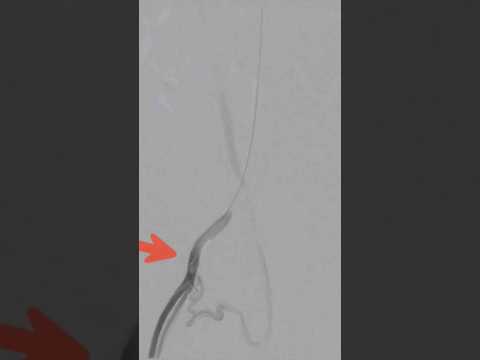

Varicocele embolization live case - Step 4 | Dr. Gaurav Gangwani